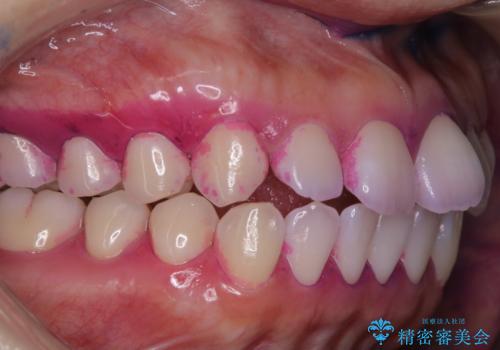

タバコによるヤニをPMTCで除去

担当医 歯科衛生士